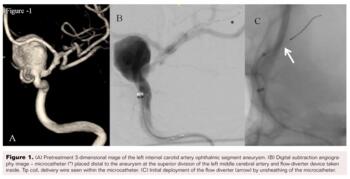

The Pipeline Flex embolization device (4.25 x 25 mm) was then deployed from the left supraclinoid ICA with an aim to jail the origin of ophthalmic artery, as per the plan (Figure 1). The check angiogram showed stasis within the aneurysm with preserved flow in the left ICA and its branches.

In the immediate postdeployment phase of the Pipeline device, the following steps were done successively:

1. After deployment of the Pipeline stent, we encountered many difficulties trying to recapture the delivery wire while attempting to resheath it. It took a moment to realize that the distal tip of the catheter had gotten stuck between the distal marker and the polytetrafluoroethylene (PTFE) sleeve. Meanwhile, we applied reasonable pull force and maneuvered the catheter to recapture the delivery wire (Figure 2).

2. Wire fracture proximal to the proximal marker was recognized by the inability to navigate and the unresponsiveness of the distal delivery wire during torquing and subsequent withdrawal of the wire (Figure 3).